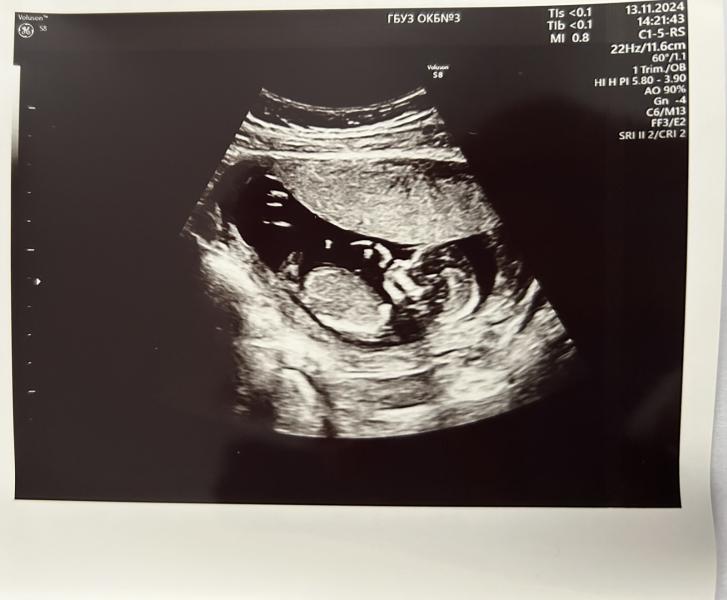

Сегодня проходила 1 скрининг в ОКБ 3, все очень добродушно, измерили давление , врач посмотрела трансвагинально и трансабдоминально , показали на экране , сделали фотографию (за доп плату) , все показатели в норме , даже предположили , что будет мальчик, но нам без разницы )